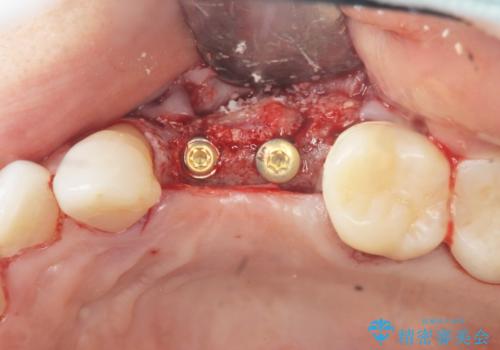

抜去後の補綴治療は長いブリッジではなくインプラント治療を希望されましたが、穿孔・破折による周囲の骨吸収をリカバリーすべく骨の造成を伴うインプラント治療を計画します。

インプラント治療を行うにはインプラント周囲に十分な骨の幅・高さが必要です。

今回はが原因で失われてしまった骨の幅を回復することで長期的な予後を見込めるインプラント治療を行うことができました。